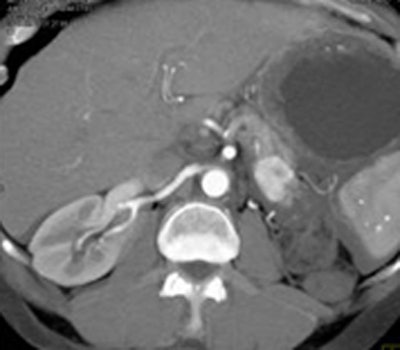

![]() |

| Patient has dilated pancreatic duct, but no tumor is visible. All images courtesy of Elliot Fishman, MD. |